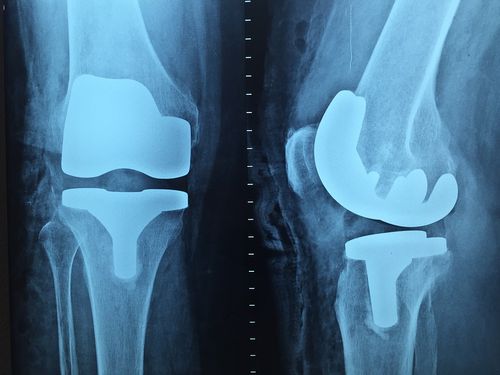

3. 영상 검사: 무릎 관절의 내부 구조를 확인하기 위해 X-선, CT, MRI 등의 영상 검사를 시행할 수 있습니다.

무릎 관절염의 치료 방법은 다양합니다. 비수술적 치료로는 체중 감량, 물리치료, 약물 치료 등이 있습니다. 수술적 치료로는 관절경 수술, 관절 치환술, 관절 절제술 등이 있습니다. 치료 방법은 환자의 연령, 증상의 심각성, 관절 손상 정도 등을 고려하여 결정됩니다.

4. 수술 치료: 위 치료 방법이 효과가 없는 경우 수술이 필요할 수 있습니다. 수술은 관절경 수술, 관절 치환술, 관절 절제술 등이 있습니다.